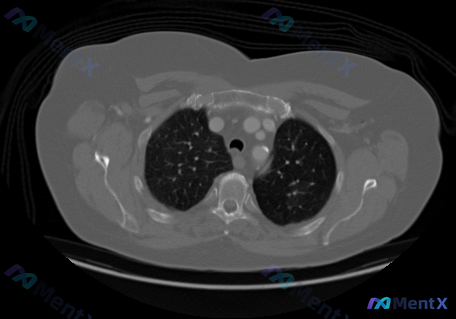

最近看到一个很有警示意义的影像分析案例,整理了一下思路分享给大家。 病例背景 用户仅提供了一张胸部CT横断面肺窗(主动脉弓层面)的图像,直接询问“这幅图像中的癌症分期是什么”。 先看这张CT的关键表现 整理了影像分析的核心阳性/阴性发现: ✅ 胸廓与纵隔:结构对称,气管居中通畅,主动脉弓壁见点状钙化...

今天看到一个挺有警示意义的“影像分析请求”,整理一下思路和大家讨论。 用户的要求很直接:识别这张胸部CT肺窗中的癌症类型、位置、TNM分期和总分期。 先看这张图像的客观表现(按报告整理) - 层面:主动脉弓层面肺窗 - 气道:气管及左右主支气管通畅,无狭窄/阻塞/壁增厚 - 肺实质:双肺透亮度好,肺...